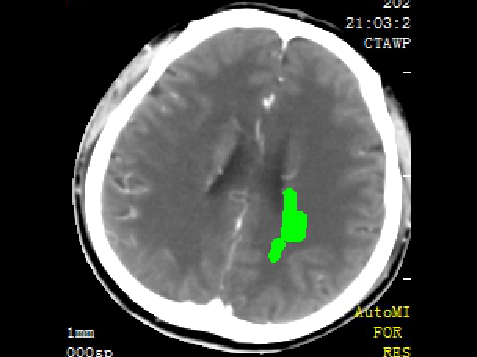

急诊予以静脉溶栓,同时完善头颈CTA+CTP、MIStar相关检查

结合CTA结果,提示左侧颈内动脉起始部至颈内动脉末端未见显影,起始部成鼠尾征改变,前交通动脉开放,双侧大脑中动脉显影良好。MIStar图像提示核心梗死灶和缺血半暗带较小,但是MTT提示左侧大脑中动脉流域区明显延长。

静脉溶栓过程患者症状逐渐减轻,构音障碍和右侧肢体活动不灵均有缓解,NIHSS评分降到2分。就在溶栓快结束时,患者突然症状再次加重,NIHSS评分10分,复查头CT未见出血。结合之前影像,不除外左侧颈内动脉急性闭塞形成血栓后脱落可能,立即启动急诊介入治疗。